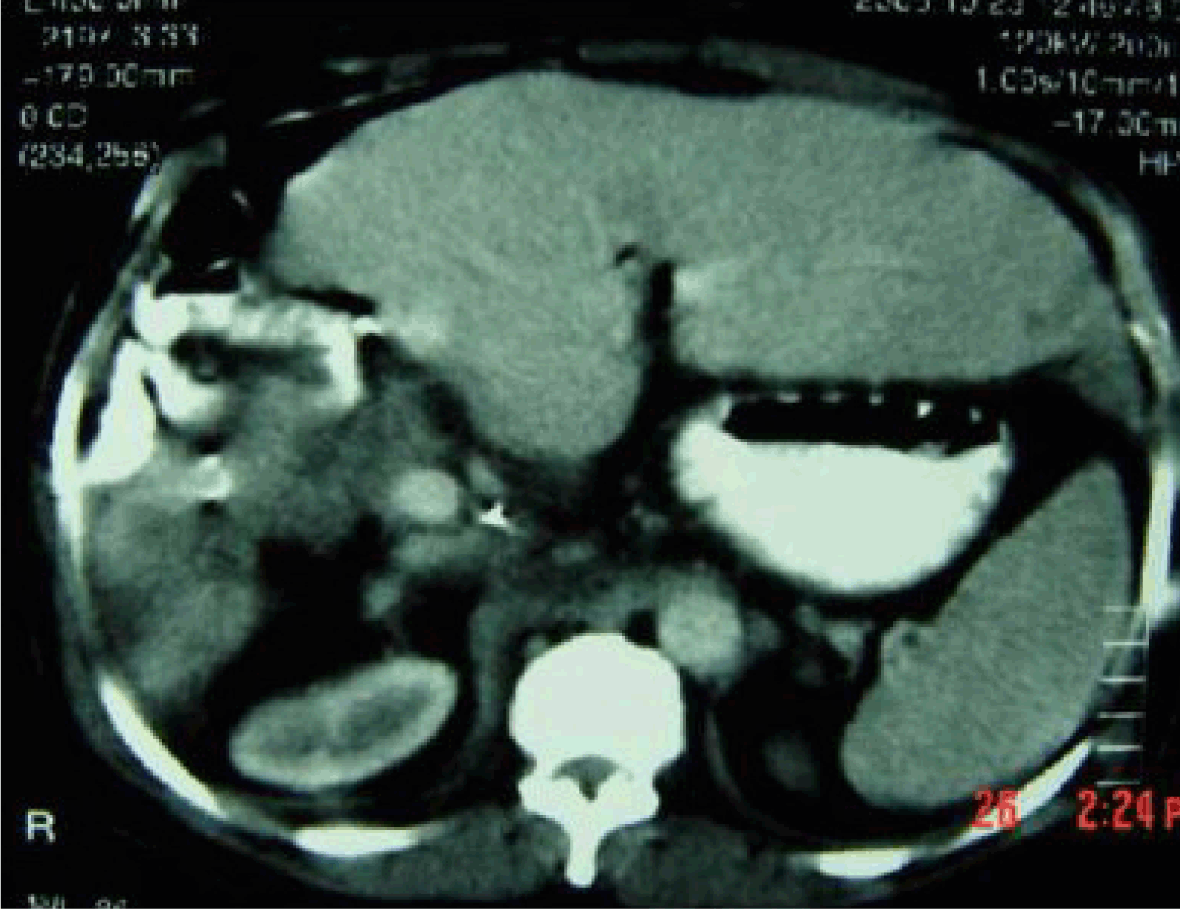

Along a period of 10 years, a 45-year-old male had been complaining of a dull aching pain stationary in course for eight years, and in the last two years, it became progressive preventing the patient from sleeping in supine position due to severe dyspnea. Also, bilateral edema of the lower limbs were noted. Abdominal examination revealed a non-tender firm intra-abdominal mass in the right hypochondrium, lumbar and epigastric regions moving with respiration. A doubtful lateral mobility was present. An ultrasound study of the abdomen showed a large well encapsulated mass in the caudate lobe of liver with caudal exophytic expansion to segment VI. Triphasic computed tomography (CT) scan demonstrated a large mass in the caudate lobe with a typical CT enhancement pattern of hemangioma. (Figure 1) The patient had excellent liver function with; serum albumin 4 g/dL, prothrombin 90%, serum bilirubin 0.8 and normal complete blood picture. With negative viral markers and normal alpha fetoprotein. Upper gastrointestinal endoscopy was free. Surgical exploration of the patient was done through a Mercedes-Benz incision which reveald huge hemangioma exophytic from the caudate lobe of the liver (Figure 2) the liver itself was healthy and of good size with evidence of small hemangiomas in the left lobe but no nodules, ascites nor lymph nodes were present. Porta hepatis dissection and transfection ligation of the feeding vessels to the caudate lobe from the portal vein and hepatic artery was done firstly, and then mobilization of the right lobe and transfixion ligation of the posterior hepatic veins which were found large in size. Then an approach of the exophytic part of the hemangioma (antecaval part and caudate process had been started through dissection along the plane between its capsule and liver tissue on the surface of the liver using harmonic scalpel after division of the cystic duct and artery. This helped to attain a bloodless field and easy dissection of that part of the tumor till its complete separation and extraction from the caudate lobe proper. The remaning part of the caudate lobe hemangioma (caudate lobe proper) appeared clearly showing compression of the inferior vena cava (IVC) and extending laterally and caudally behind the porta hepatis with the gastrohepatic ligament obviously stretched in between the hemangima and segment II, III. (Figure 3) Approach to this part was done from both right and left sides, after division of the gastrohepatic omentum and the ligamentous attachments from the caudate lobe to the left side of IVC, the tumor was completely separated from the IVC lateraly and from the middle and left hepatic veins superiorly allowing reasonable rotaion and delivery of the tumor through the left side. (Figure 4) Transcystic cholangiogram was done and revealed patent sound biliray system. This bloodless procedure was done without any total or partial vascular isolation or occlusion and without blood transfusion. The time of surgery was 4 hours and 20 minutes. The abdomen closed with tube drain. The patient passed a smooth postoperative period and was discharged 10 days after surgery. Histopathological examination of the tumor revealed cavernous hemangioma. (Figure 5) Three weeks later spiral CT scan was done which revealed complete removal of the tumor. (Figure 6)

Figure 1: Arterial phase triphasic computed tomography scan showing large caudate lobe mass with peripheral nodular enhancement pathognomenic for hemangioma.